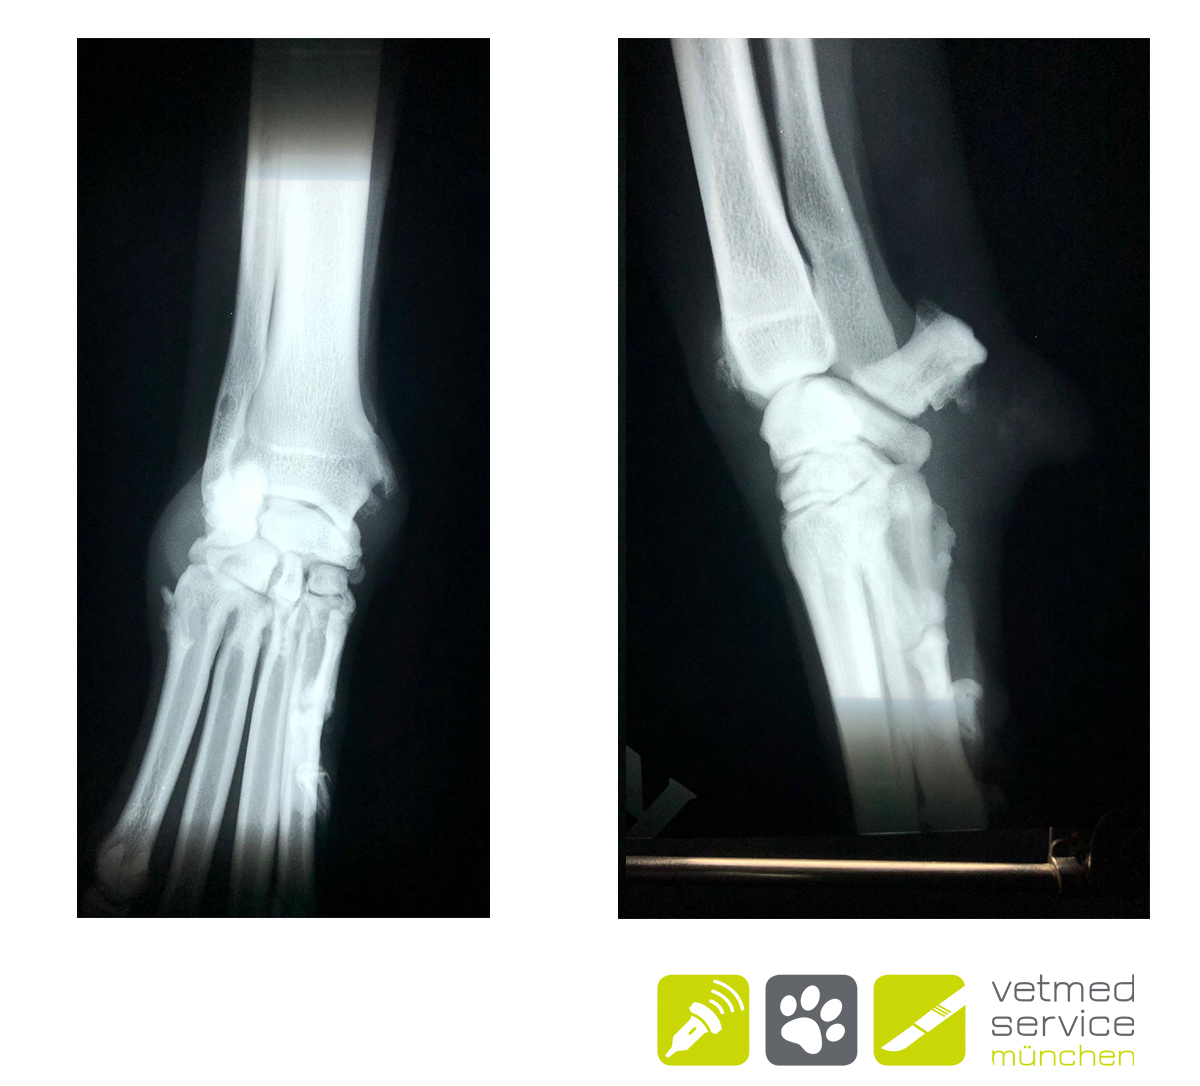

Röntgenologisch zeigten sich Exostosen am medialen Karpus. Das typische Bild einer Tendovaginitis des M. abductor pollicis longus. Da die konservativen Versuche erfolglos blieben, wurde bei „Emma“ eine operative Therapie durchgeführt. Wir haben die Phalanx I amputiert , die Sehne des M. ext. dig. longus freigelegt diese am Übergang zum Muskelbauch abgesetzt, sowie die Exostosen abgetragen. „Emma“ lief bereits kurze Zeit nach der OP lahmheitsfrei und ist es bis heute (7 Monate post OP)

"Meinst du das könnte ein Knochentumor sein und machst du auch Knochenbiopsien?" - Eine berechtigte Frage, beim ersten Blick auf das beigefügte Röntgenbild, denn die röntgenolgischen Veränderungen dieser Erkrankung können an ein Osteosarkom erinnern. Aber es handelt sich um eine Tendovaginitis des M. abductor pollicis longus💡. Obwohl der "Daumen" des Hundes beim Laufen gar nicht wirklich belastet wird, kommt eine chronische Entzündung dieser Sehnenscheide immer wieder vor und führt zu einer chronisch rezidivierenden Lahmheit und zu einer halbkugeligen Schwellung am kraniomedialen Antebrachium. Die röntgenologisch sichtbaren Metaplasien können dem Bild eines Osteosarkoms ähneln. Vergleichende Röntgen der Gegenseite helfen bei der Beurteilung. Falls eine Therapie mit NSAIDs nicht zielführend ist, kann bei schweren Fällen eine Amputation der ersten Zehe und Entfernung der Metaplasien sinnvoll sein.